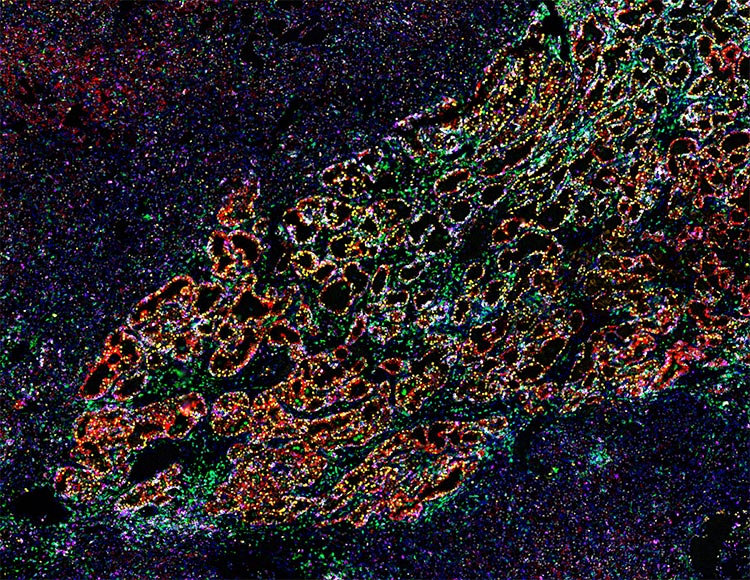

Orion 18 plex imaging of breast duct harboring ductal carcinoma in situ. Image courtesy of Aditi Khatpe, Stanford University.